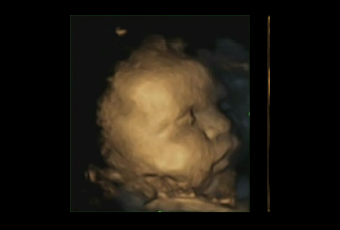

L’émotion de douleur n’apparaît chez le fœtus qu’à la 25e semaine à cause de la maturation du système cortical. L’expression faciale typique de la douleur étant : le froncement des sourcils, froncement du nez, élévation de la lèvre supérieure, ouverture des lèvres (AU4+9+10+25). Voir photo ci-contre.